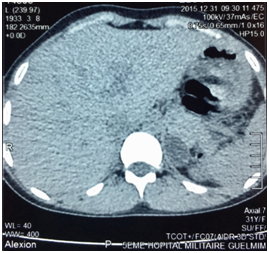

E.O. was a 31-year-old female, with a history of celiac disease under gluten-free diet, and a pregnancy-induced hypertension one year ago, without having been screened for secondary hypertension, to the best of our knowledge. A satisfactory blood pressure (BP) has been reached under treatment with nicardipine (100mg/day). The patient was admitted to our hospital because of headache, muscle weakness and heart palpitations, for two weeks. On physical examination, the patient was in regular general condition and with a healthy coloring. Her weight was 53.5 kg and height 162 cm (BMI=20.41Kg/m2). Blood pressure measured with a manual armlet 190/110 mmHg, heart rate 100beats/minute and regular, respiratory rate 18cycles/min, body temperature 36.9°C. On auscultation, her lungs were clear with no rales. Her heart auscultation showed regular cardiac rhythm with cardiac sounds of normal intensity and no murmurs. Her lower limbs showed symmetric palpable pulses and no edema. The power and sensation of both lower and upper limbs were normal. The abdominal examination showed hydro-aerial noise, no visceromegaly and no abdominal murmur. Thyroid gland examination was normal. There was neither obesity nor hirsutism. Other physical examination was normal. Laboratory findings were as follows: serum potassium 1.68mEq/L (normal range (NR)= 3.5-5.1), sodium 143 mEq/L (NR=136-145), alkaline reserve 32mEq/L(NR=22-31), corrected calcium 95mg/L(NR=86-100), phosphorus 29.9mg/L (NR=25-45), urea 0.15g/L (0.13-0.45), creatinine 3.9mg/L(NR=5-9). The complete blood count and coagulation indices were normal. The thyroid function test was normal (0.94mU/L; NR=0.27-4.2). The measurements of sodium and potassium in the 24-hour urine were 54mEq/L (NR=54-190) and 63 mq/L (NR=25-125), respectively. The ECG showed presence of changes of hypokalemia, U waves and no hypertension changes. Echocardiography assessment of hypertension was negative, and there was no hypertension retinopathy. She was treated with boluses of intravenous potassium chloride and oral potassium supplements, for 260 mmol/day over 6 days. Initially her hypertension was treated with intravenous nicardipine utilizing an electrical syringe pump. Despite intravenous and oral potassium supplementation, her serum potassium level remained low. The PA was suspected because of persistence hypokalemia in association with hypertension and alkalosis. However, after correction of serum potassium level, the patient was examined for the plasma aldosterone concentration (PAC) and direct rennin concentration (DRC). Results revealed a low DRC level of 0.9mUI/L (NR=2.8-39.9), along with a very high PAC level of 2613pmol/l (NR=83-405). The aldosterone to rennin ratio (ARR) was 523pmol/l per mUI/l (N<64). Subsequently, after a three-day oral sodium load, 24-hour urine was tested for the concentration of sodium (260mmols) and aldosterone (27.3mg). Abdominal computerized tomography (CT) revealed a 28x21 mm hypo-dense mass (1UH of density), not enhanced by the contrast product, over the left adrenal gland (Figures 1) (Figures 2). After using spironolactone 100 mg/day and nicardipine 150 mg/day for one month preoperatively, the BP normalized (BP=125/85 mmHg), the headache, weakness and heart palpitations significantly improved, and the serum level of potassium was 4.5 mEq/L. Therefore, the patient underwent a successful laparoscopic left adrenalectomy (Figure 3), and the postoperative course was well. The macroscopic tumor consisted of an ovoid piece of yellow color tissue with weight: 28gr, circumscribed mass: 20x30mm in dimensions adjacent to adrenal tissue. Histologically, the adrenal mass showed an encapsulated epithelial neoplasia with cells of clear cytoplasm, round nuclei and conspicuous nucleoli. However, necrosis, capsular invasion and atypical mitosis were not found (Figure 4). The anatomic pathological diagnosis was adenoma of the adrenal gland consistent with Conn’s adenoma. The patient was normotensive and serum potassium was 4.5mEq/L without any antihypertensive medication or supplement for the last three months after discharge. She was stable with a optimal control of blood pressure without hypokalemia with a 2-year follow-up.

PA is the cause of approximately 0.05-2% of all secondary arterial hypertension is characterized by suppressed plasma renin activity and hypokalemia.3 Conn estimated the prevalence of the disorder around 10% of the general population.4 PA includes unilateral adenoma (=APA) (30%), unilateral (2%) and bilateral (60%) adrenal hyperplasia, familial aldosteronism (1%) and adrenal carcinoma with aldosterone hyper secretion (<1%). The uncontrollable synthesis of aldosterone leads to increased sodium reabsorption, kaliuresis and renin suppression. All of the above challenge arterial hypertension, which affects target organs (heart, kidneys, brain) more gravely than essential hypertension does.5 The APA is a small nodule (< cm) that mostly occurs in the left adrenal gland commonly found in females, and usually present with severe hypertension and more profound hypokalemia. It is also more common in younger patients (30-50 years of age), with higher plasma and urinary levels of aldosterone.6 Some patients are completely asymptomatic or have minimum symptoms resulting from hypertension (headache) and hypokalemia (polyuria, nocturia, muscle cramps). Occasionally, excessive muscle weakness, paresthesias, tetany, and even muscle paralysis may occur.2,7,8 Usually, PA is characterized by hypertension, hypokalemia, excessive urinary excretion of potassium, hypernatremia, and metabolic alkalosis.7 It is recommended testing for the PA in the following groups: patients with hypertension and hypokalemia, treatment-resistant hypertension (three antihypertensive drugs and poor control), severe hypertension (>160 mmHg systolic or>100mmHg diastolic), hypertension and an incidental adrenal mass, and onset of hypertension at a young age.6 We described a case of young (31 year-old) female with a pregnancy-induced hypertension one year ago, without having screened for secondary hypertension, and with satisfactory control of blood pressure under treatment with nicardipine, which favors the initial diagnosis of controlled primary hypertension, despite its beginning at an age suggesting secondary hypertension. The occurrence of hypertension crisis with headaches, muscle weakness, heart palpitations, and significant hypokalemia led us to consider a cause of hypertension secondary in origin superimposed on primary hypertension. Despite intravenous and oral potassium supplementation, her serum potassium level remained low. The PA was suspected because of persistence hypokalemia in association with severe hypertension and alkalosis. Hypokalemia (serum potassium ≤3.5mmol/l) is only present in a minority of patients with PA.9 However; the frequency of hypokalemia is related to whether PA can be surgically cured. A study with a large series of patients reported that hypokalemia was present in 7%, 17% and 48% of patients with essential hypertension, idiopathic PA, and APA, respectively.10 Our patient had an association of PA secondary to APA, and celiac disease under gluten-free diet. This association has never been described in the literature. Both diseases can manifest as hypokalemia, PA by excessive urinary excretion of potassium, and celiac disease by mal absorption, which could trigger or aggravate hypokalemia. The diagnostic approach of PA can be consisted in three steps: the ARR calculation, confirmatory tests of PA and distinction of the disease subtypes. Recent guidelines suggest screening for PA patients with difficult-to-treat or hypokalemic hypertension using the ARR.9 The ARR was introduced by K Hiramatsu and colleagues in 1981 as a screening tool to facilitate the diagnosis of PA among hypertensive patients.11 Although, using the ARR decreases the intra- and inter-patient variability in renin and aldosterone levels linked to sodium intake, body position and age.12,13 The most frequently used cut-off values for PAC to PRA ratios are in the range of 20 to 50ng/dl (554 to 1.385pmol/l) per ng/ml.h; for PAC to DRA, these values are in the range of 2.4 to 4.9ng/dl (66 to 136pmol/l) per mU/l.14 Our patient had a two ARR greater than 136pmol/l per mUI/l. The recent clinical practice guidelines for case detection, diagnosis, and treatment of patients with PA recommend that patients with positive ARR undergo any of four suppression tests to confirm or exclude the diagnosis of PA.14This implies that PA is defined as a non-suppressible aldosterone excess. The four suppression tests respectively use oral sodium loading, oral fludrocortisones, oral captopril, or saline infusion to suppress aldosterone secretion.9 Oral sodium load test includes the determination of sodium and aldosterone concentration in 24-hour urine, after 3 days of increased salt intake. Rates of aldosterone >12mg and sodium>200mmols are diagnostic of PA.6 This test confirmed the presence of PA in our patient (Aldosterone: 27.3mg/24h, Sodium 260mmols/24h). We did not proceed to saline infusion test (intravenous infusion of 2 liters of saline in four hours leads to a PAC rate over 277pmol/l if PA is present), oral captopril test and fludrocortisones test. The fludrocortisones suppression test is rarely performed in most centers nowadays.6 Distinction of disease subtypes is based on CT, adrenal vein catheterization with venous sampling and genetic screening for the familial types of the disease.14 In our patient, abdominal CT demonstrated a 28x21 mm hypo-dense mass (1UH of density), not enhanced by the contrast product, over the left adrenal gland. Unenhanced attenuation values on CT<10 UH indicated adenoma, as carcinoma present with values over 10 HU.15 The presence of an adenoma in patients with PA suggests the presence of an APA, but it cannot exclude the combination of a non-secreting adenoma and idiopathic PA.14,16 For distinction of the disease subtypes, a more practical approach use for the adrenal vein sampling (AVS) as recommended by Young.6 which is based on patient preferences, age, adrenal morphologic appearance on CT, clinical comorbid conditions, and clinical probability for finding an APA. For patients younger than 40 years, in whom a solitary adenoma is >1cm with normal contralateral adrenal gland, a unilateral adrenalectomy may be done without AVS and in the absence of comorbid conditions. Therefore, the AVS was bypass in our case based on these criteria.